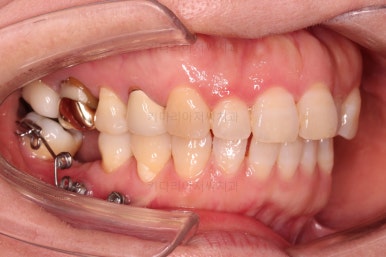

초진 시 입안의 모습입니다.

아랫니 큰 어금니 하나가 없어서 임플란트를 원하셨던 환자분이셨어요.

앞니가 조금 삐뚤고, 아랫니는 사이사이에 틈새가 있었지만 전체적인 교정은 원치 않으셨어요.